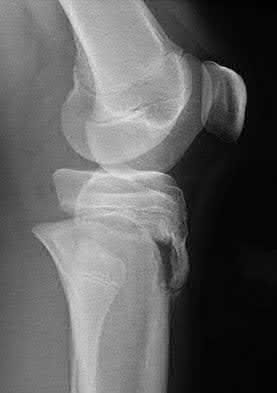

A 22-year-old male cyclist was struck by a car. He complains of right knee pain and swelling, as well as reduced sensation and weakness in his right foot. His leg compartments are soft and not tender. Distal pulses in the extremity are palpable. Radiographs of the knee, as shown in Figures A and B, were taken after a closed reduction maneuver was performed. What would be the next best step in management of this patient?

This patient presents with a Schatzker IV tibia plateau fracture with lower extremity neurologic deficits. The next best step would be to investigate for an acute vascular injury with ankle-brachial index measurements.

Fracture-dislocations of the knee must be suspected with all Schatzker type IV injuries as this fracture pattern is usually associated with high energy trauma. Identifying this injury should prompt a thorough assessment of the neurovascular structures across the knee. After closed reduction and emergent immobilization of the knee, ankle brachial indices (ABI) must be immediately performed. If

Knee dislocations are associated with popliteal artery injury in 18-45% of cases and range from intimal tears to complete transection. Amputation rates of 85% have been reported if revascularization is delayed greater than 6 to 8 hours.

Neurologic injury occurs in 15-40% of cases and is most common after posterolateral dislocation. The peroneal nerve is more commonly injured.

Rihn et al. reviewed the acutely dislocated knee. They recommend a vascular consult if pulses are weak, or ABI is compromised. They warn that in arterial injury, pulses, temperature and capillary refill can be normal. If the limb remains ischemic, surgical exploration and revascularization is indicated.

Medina et al. systematically reviewed neurovascular injury after knee dislocation in 862 patients. Vascular injury rate was 18%, and nerve injury rate was 25%. Repair was performed in 80% of vascular injuries, and amputation in 12%. The most vascular injury was seen in KDIIIL injuries (32%) and posterior dislocation (25%).

Figure A is an AP radiograph of a posterior knee dislocation. Figure B is a lateral showing the same injury.